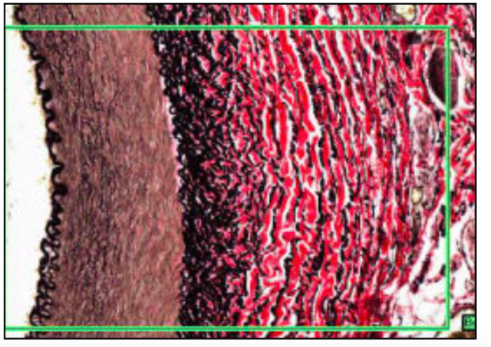

ELASTIC ARTERY (WITH MALLORY’S STAIN)

- elastic - red / collagen & muscle - blue

- = aorta and GT vessels close to heart

- medial layer thick w/concentric sheets of elastic interspersed w/smooth muscle

- as vessels large - contain own blood supply vasa vasorum

at top = intima then internal elastic lamina, then vascular endothelial cells on BM

ELASTIC TISSUE (ELASTIC VAN GIESON’S WITH IRON HAEMATOXYLIN COUNTER STAIN

- elastic tissue in tube like sheets - elastic lamina

- elastic = black

- sm = mushroom

- collagen = pink